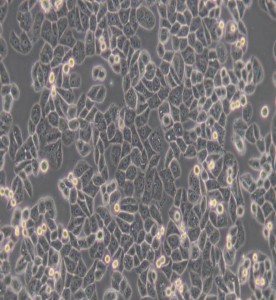

MDA-MB-468人乳腺癌細胞(DMEM)主圖

MDA-MB-468人乳腺癌細胞(DMEM)

細胞形態(tài) : 上皮細胞樣

生長特性 : 貼壁細胞